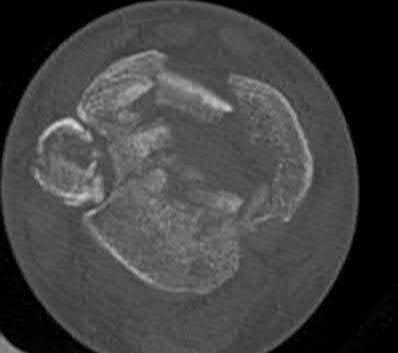

Question 19

A 28-year-old male sustains a closed comminuted tibial shaft fracture.

Two hours post-injury, he develops severe leg pain unyielding to narcotics. His blood pressure is 120/80 mmHg. Intracompartmental pressure monitoring is performed. Based on current guidelines, which measurement dictates an emergent 4-compartment fasciotomy?

Explanation

Acute compartment syndrome is classically defined by tissue hypoperfusion. The absolute compartment pressure is less reliable than the differential pressure (Delta P). A Delta P (Diastolic Blood Pressure minus Compartment Pressure) of less than 30 mmHg is an absolute indication for emergency fasciotomy, as capillary perfusion gradient is lost when tissue pressure approaches the diastolic pressure.